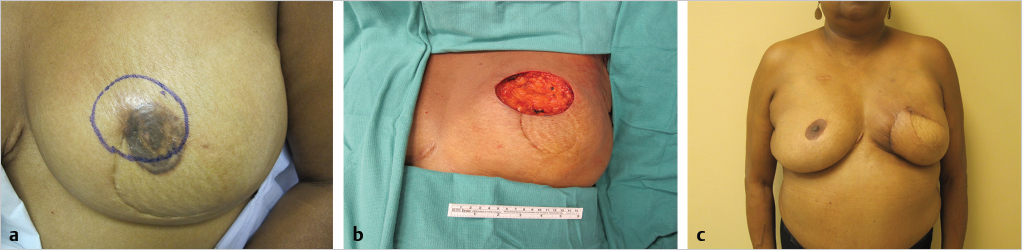

Surgical options following LR after breast reconstruction depend on the location and number of metastatic deposits and previous treatment. Imaging of the reconstructed breast and body scans are necessary to delineate the extent of tumor involvement (▶Fig. 4.4). Isolated LRs can be treated with removal of as much reconstructed tissue as necessary to achieve negative margins. Adjuvant chest wall radiation is usually administered (▶Fig. 4.5).